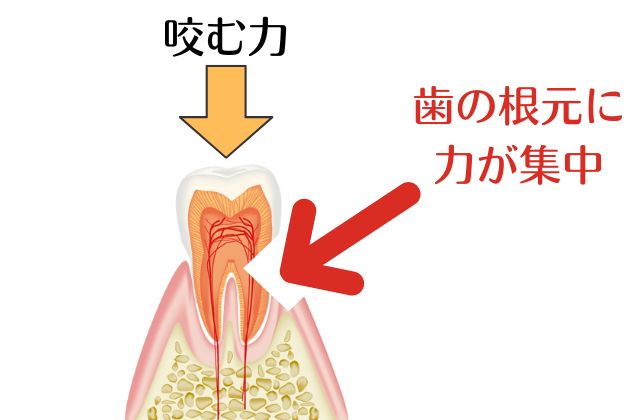

日本人が歯を失う第一位は皆様よくご存じの「歯周病」です。そして第二位は「虫歯」。そして意外に知られていないのが「歯根破折(しこんはせつ)」です。歯の根っこにヒビが入ってしまった状態のことを言います。

✅歯の根っこにヒビが入ってる

✅歯の根っこに亀裂が入っている

✅歯の根っこが折れている

✅歯の根っこが割れている

このような状態の場合一般的な歯科治療ではほぼ99%「抜歯です」という診断を受けます。歯の根にヒビや亀裂が入るとどうして「歯を抜かないといけない」ことになるのでしょう?その理由はばい菌が侵入してしまうから、です。

ばい菌が歯の根から侵入し骨や歯周周辺組織を破壊していくからなのです。しかし状態によって歯を抜かずに残せることができます。ご自身の歯はできるだけ抜かずに残したいというお気持ちがおありの方の方が多いのではないでしょうか?歯を抜かずに残せるどうかの抜歯の基準ですが実は歯医者さんによってさまざまです。歯を抜かないといけないと診断されたが抜かずに治療することはできないか?ということで吉本歯科医院にご相談にお越しになられる患者さんは非常に多いです。